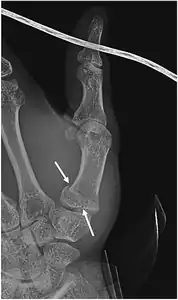

- For Bennett fractures where there is between 1 mm and 3 mm of displacement at the trapeziometacarpal joint, closed reduction and percutaneous pin fixation (CRPP) with Kirschner wires is often sufficient to ensure a satisfactory functional outcome. The wires are not employed to connect the two fracture fragments together, but rather to secure the first or second metacarpal to the trapezium.